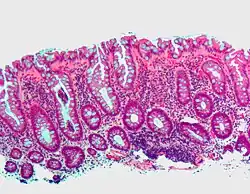

| Tubulovillous adenoma | 20% to 25%[15] | 25–75% villous[14] |

| |

- Tubulovillous adenoma: 20% risk of cancer